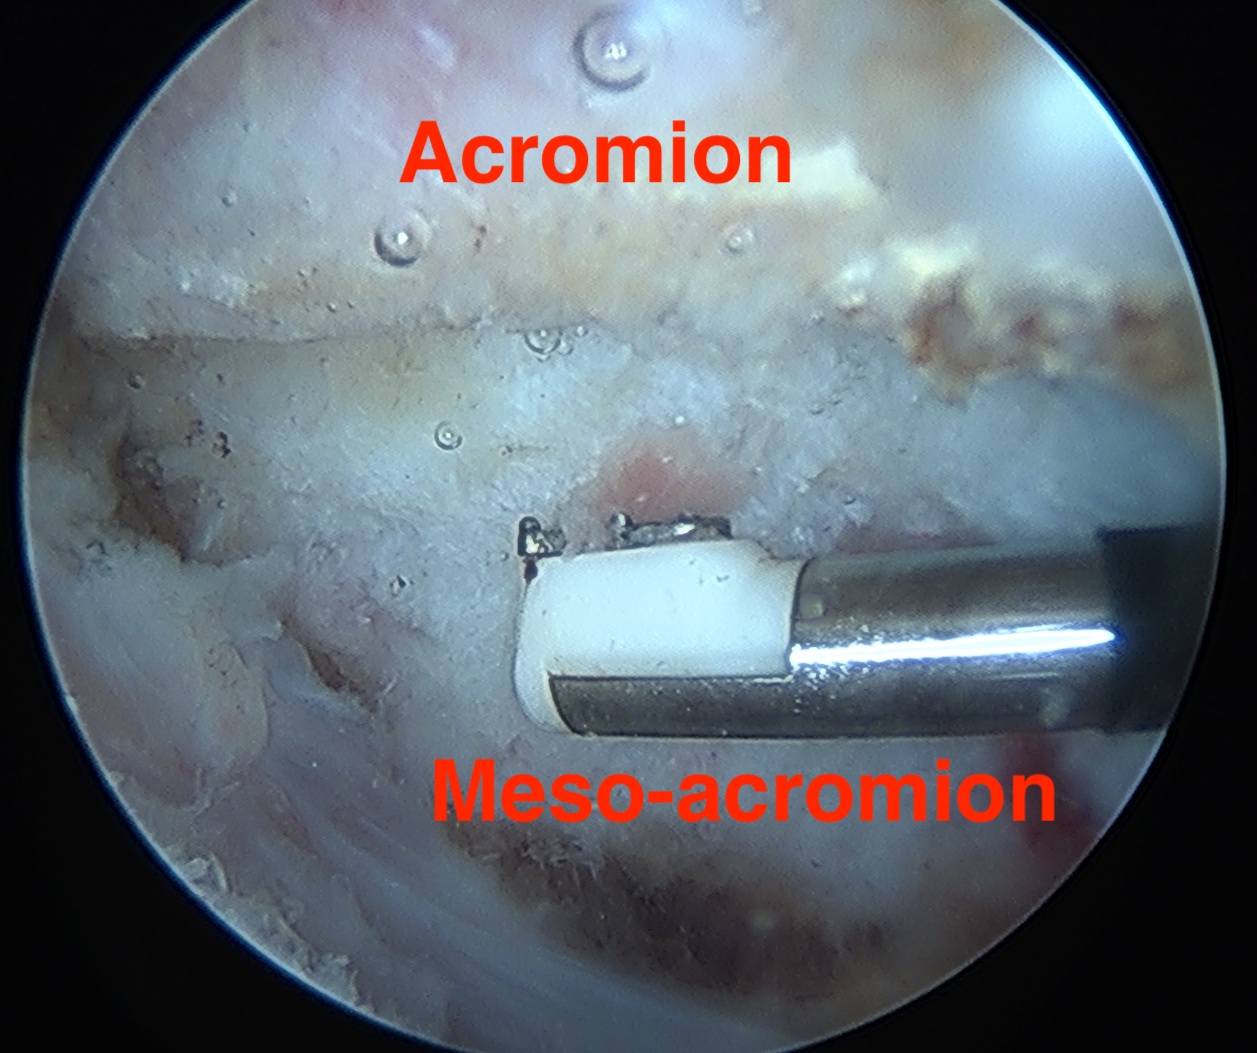

1. Meso-Acromion

- most common (94%)

- level with posterior aspect clavicle

Arthroscopic - leaves deltoid attach intact

Vumedi video arthroscopic excision of os acromiale